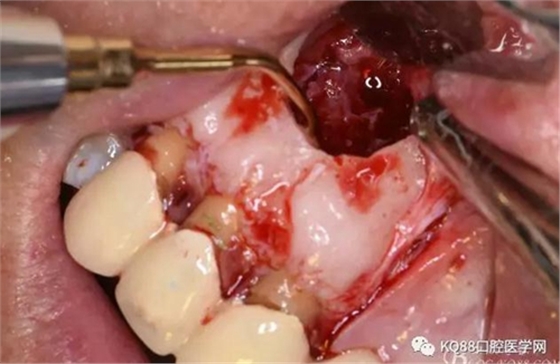

圖11.摘除囊壁后形成的骨腔

圖12.超生骨刀切除12根尖